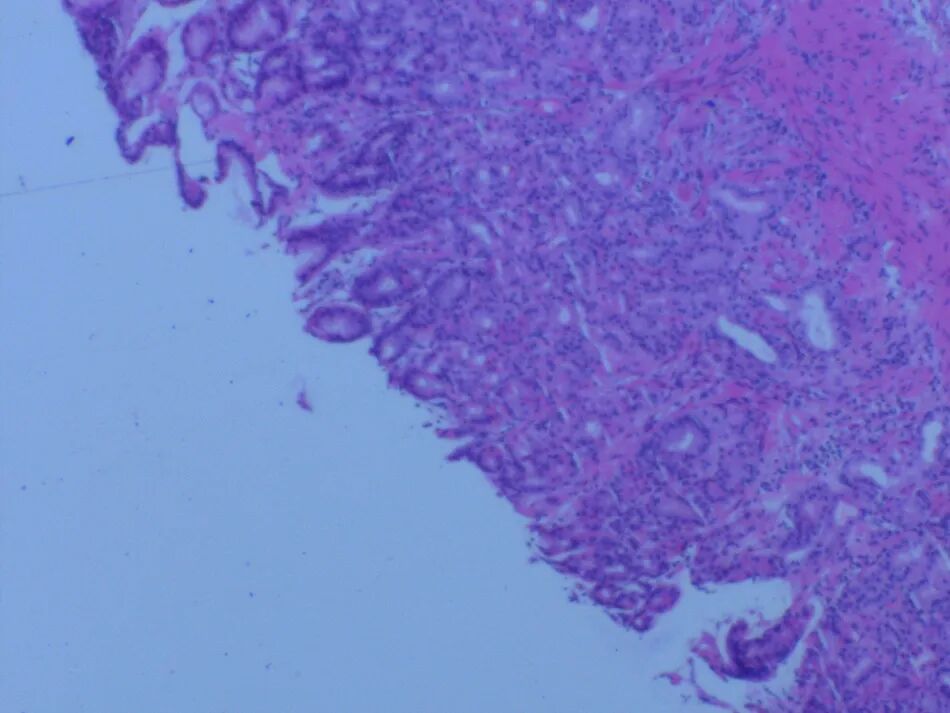

行上消化道内镜检查显示,胃体、胃大弯及前壁黏膜充血水肿(图5)。胃黏膜活检提示轻度慢性浅表性胃炎伴轻度急性活动性(图6),活检培养检出耐碳青霉烯鲍曼不动杆菌。

图6 胃黏膜活检示轻度慢性浅表性胃炎伴轻度急性活动性